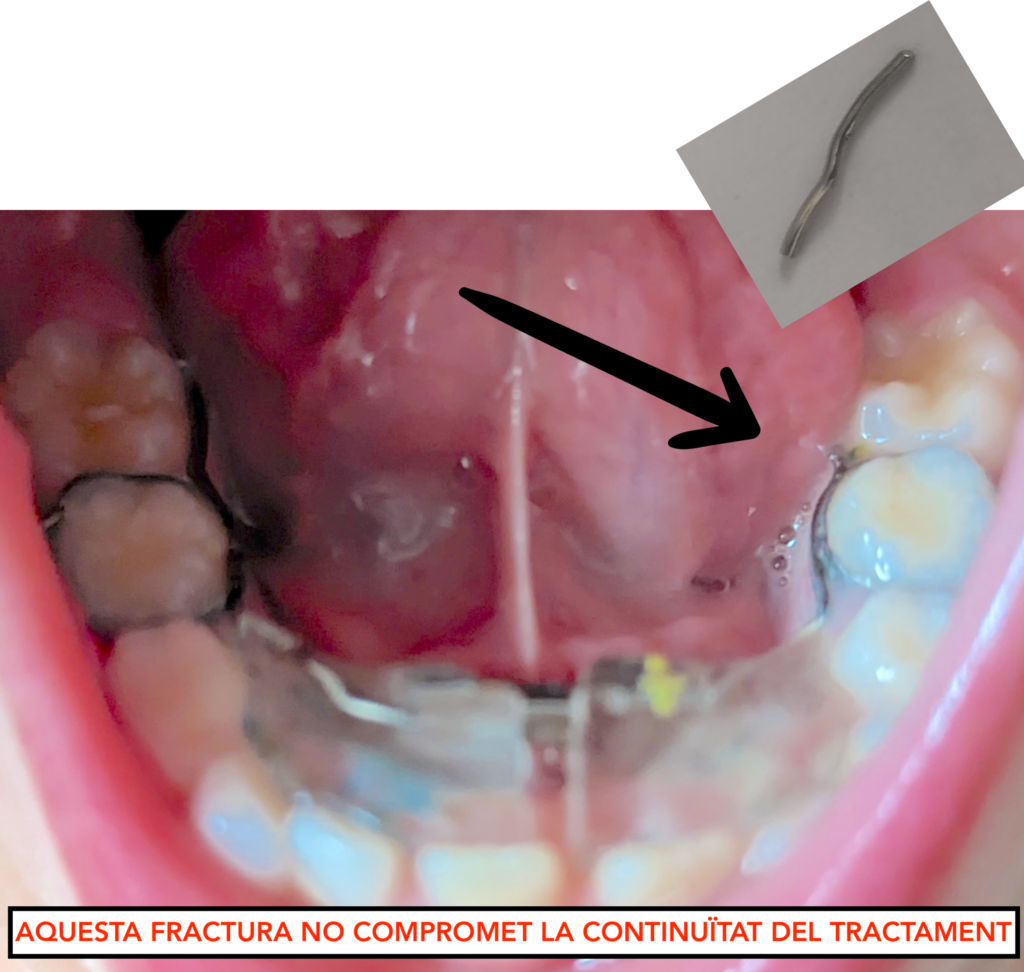

5. Fractura de l’aparell

Els aparells estan fabricats en un laboratori de plena confiança i amb materials d’alta qualitat. No obstant, estan sotmesos a forces masticatòries i d’altres tipus i en ocasions es poden fracturar.

Hi ha fractures que comprometen la continuïtat del tractament i d’altres no.

– Si detecteu alguna fractura de l’aparell –> envieu-nos un email + foto de l’aparell a: pacients@ipocubric.com

Aparell correcte

Aparell trencat